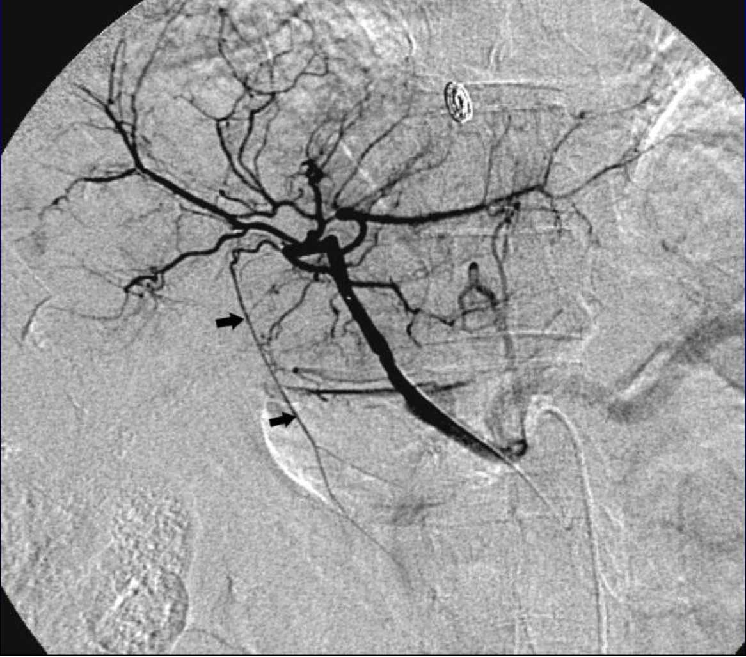

| 挽救性CRC,多灶性,肝右叶病灶一次性治疗 scout dose (低剂量或侦查剂量)右肝动脉【Nima Kokabi 2022 最新的进展】

治疗后,低剂量(侦查剂量) vs 治疗剂量

注意肝左动脉(特别是,异位肝左动脉(replaced left hepatic artery))

有问题的血管